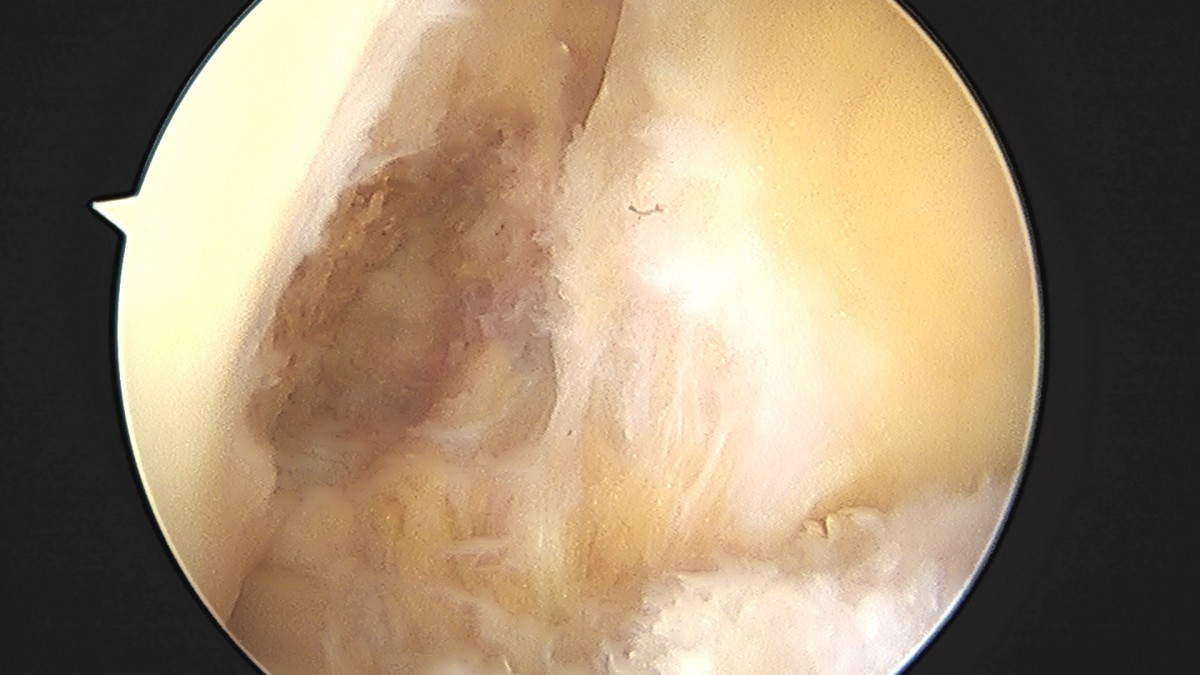

이재상원장님 무릎 전방십자인대 재건술 김태O 환자

작성자 최고관리자 댓글 0건 조회 679회 작성일 25-09-16 16:23